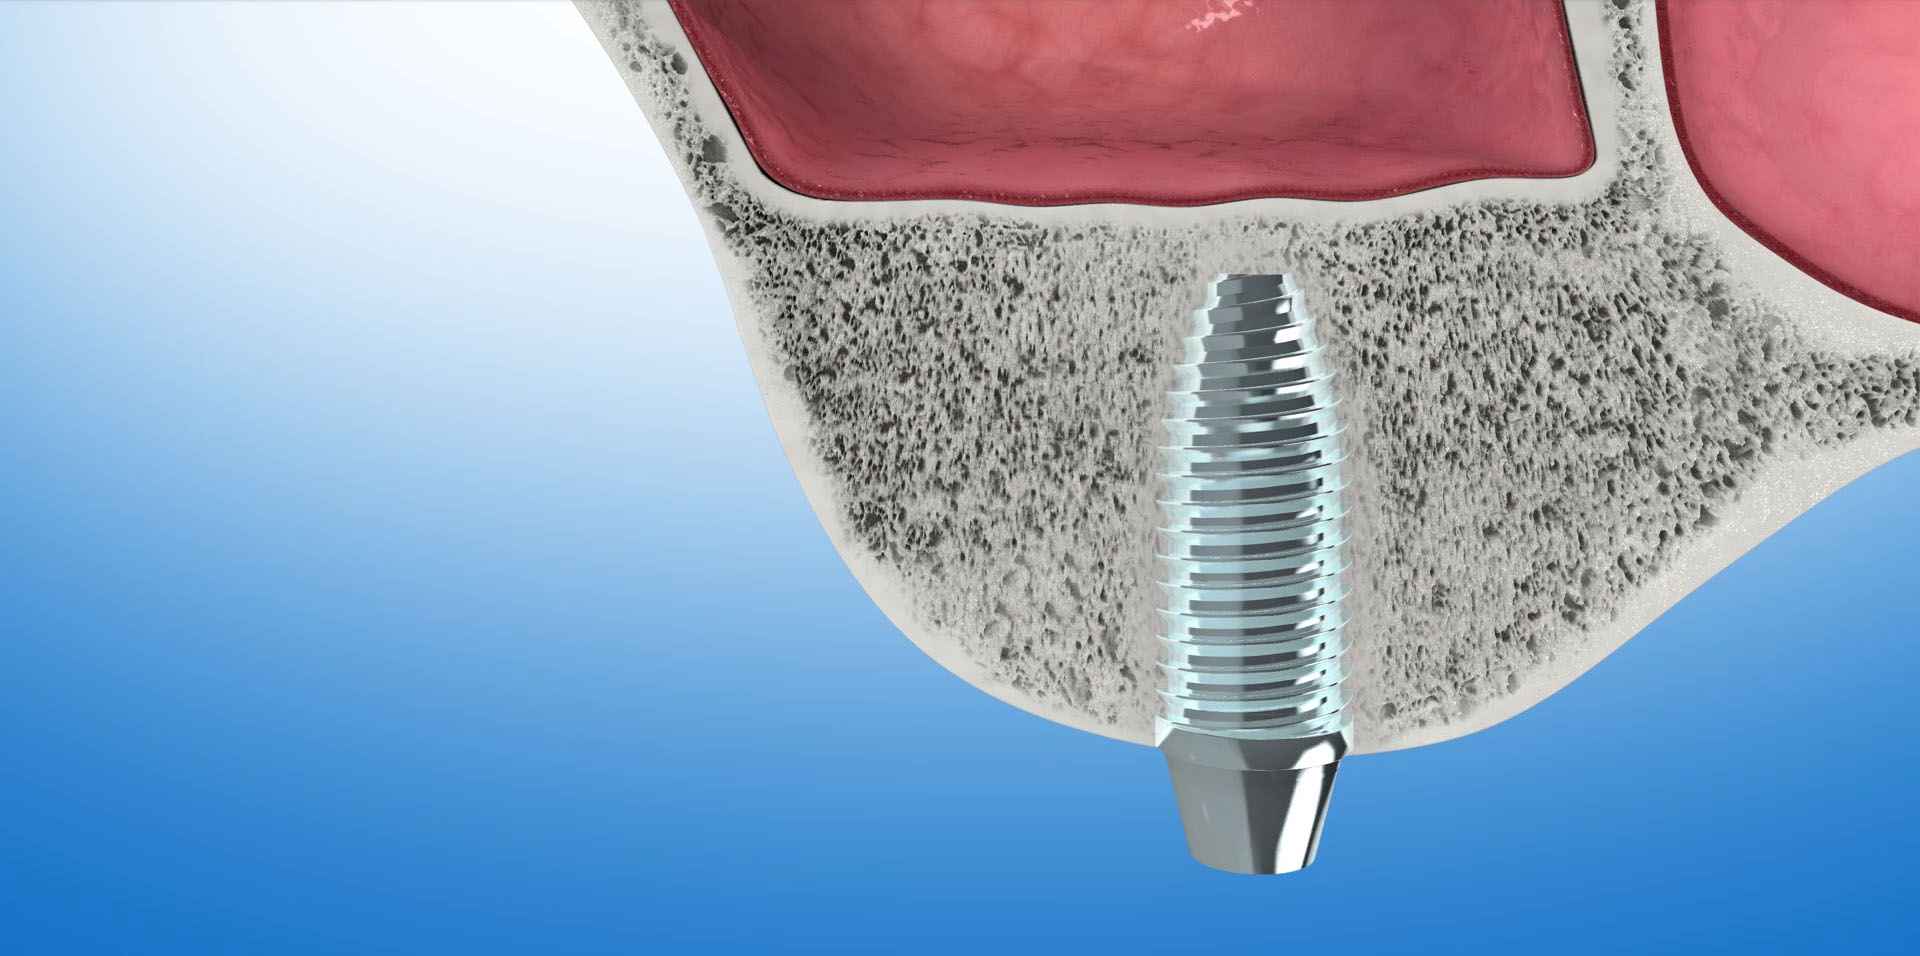

STEROWANA REGENERACJA KOŚCI (GBR-guided bone regeneration)

To odbudowa kości pacjenta do poziomu umożliwiającego implantację. Zanik kości wyrostka w wymiarze pionowym i poziomym powoduje powoduje w efekcie to, że jest on za niski lub zbyt wąski aby można było umieścić w nim implant dentystyczny. Ok. 40% przypadków wszystkich zabiegów implantacyjnych wymaga regeneracji kości. W jej wyniku odbudowana kość będzie stanowiła odpowiednie oparcie dla implantu oraz znacząco poprawi wynik estetyczny leczenia.

To materiał kościozastępczy produkowany z kości wołowych. W trakcie procesu produkcyjnego usuwane są z niego wszystkie składniki mogące powodować przenoszenie chorób lub wywoływać reakcje alergiczne. Naturalna struktura mineralna zostaje jednak nienaruszona. Wykazuje ona ogromne podobieństwo do struktury kości ludzkiej. Ten porowaty materiał o utkaniu ludzkiej kości stanowi doskonałe rusztowanie dla naczyń krwionośnych i komórek kościotwórczych. Stanowi matrycę, sieć dla tworzącej się tkanki kostnej. Z upływem czasu, ok.1mm w ciągu miesiąca, Bio-Oss ulega resorbcji, a miejsce po nim zajmuje nowo wytworzona kość.